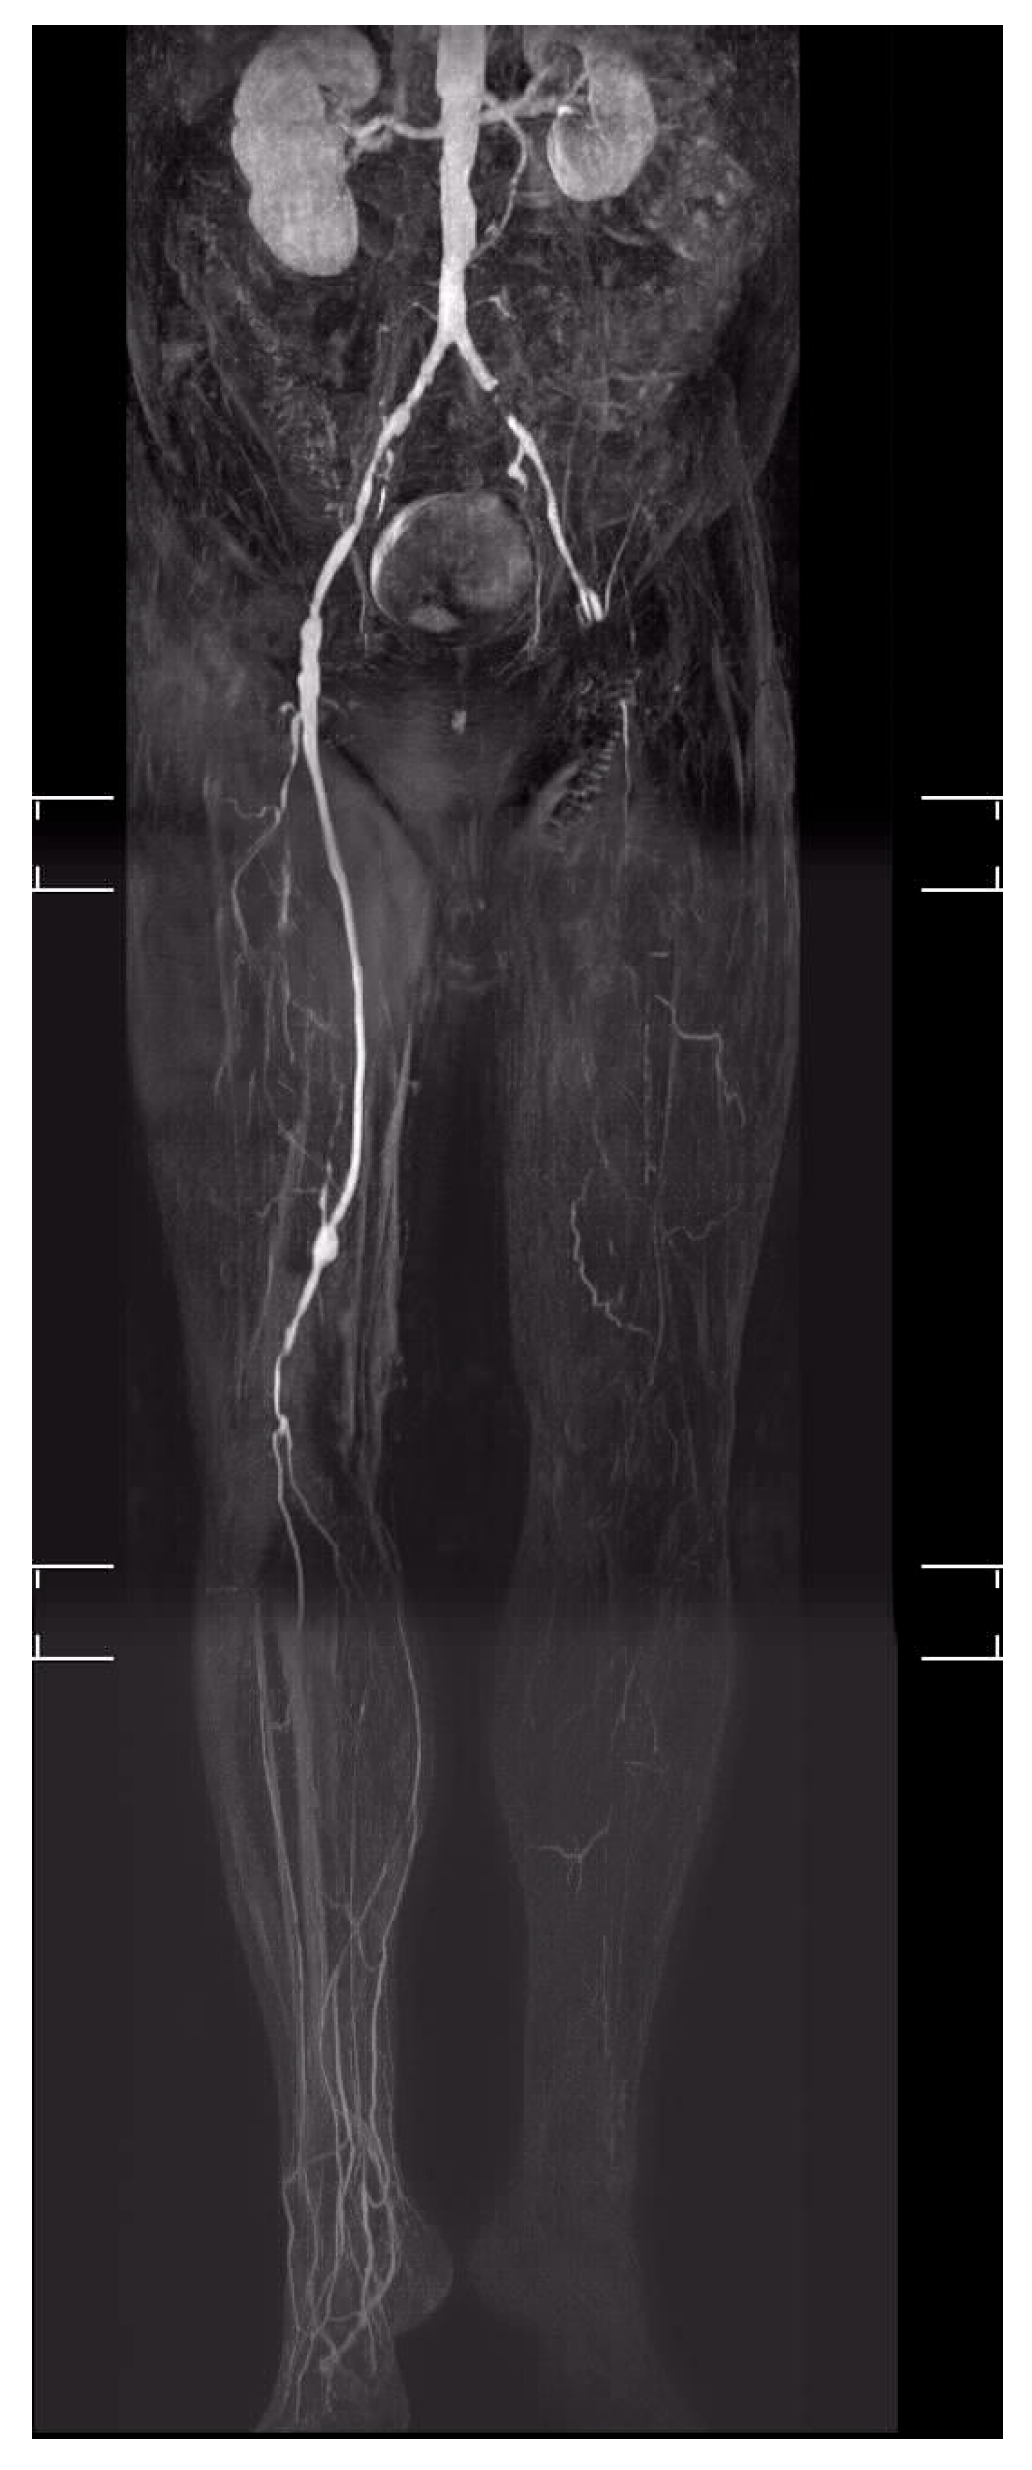

4. Treatment of CLTI

5.12. Arterialisation of the Deep Leg Veins (DVA or Deep Vein Arterialisation)